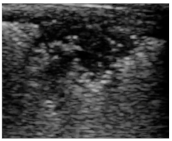

2.4. Analysis of Consolidations in 2D

3.2. Analysis of the Consolidations